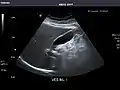

Aorta: Visualized portions normal in caliber, 16 x 15 mm.

Aorta